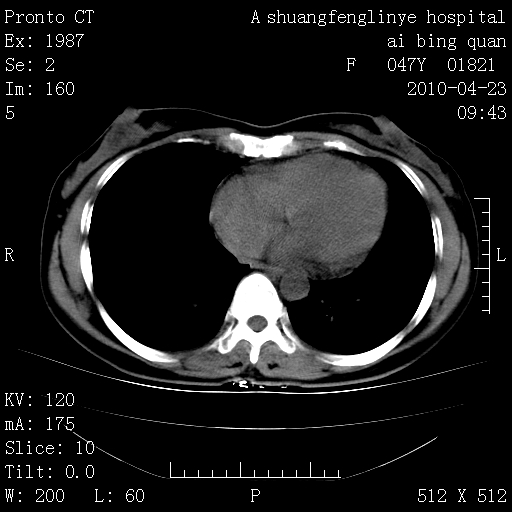

标题: CT25944:胸痛、气短、前几日高烧!肺Ca?请会诊! [打印本页]

标题: CT25944:胸痛、气短、前几日高烧!肺Ca?请会诊!

kaolv 周围型肺癌并同肺转移

双肺多发结节,考虑转移瘤,肺癌肺转移不除外

周围型肺癌并肺转移

双肺多发结节,部分密度较高,最大结节边缘光滑。临床有“胸痛、气短、前几日高烧”病史。首选考虑:右肺感染性病变!建议积极消炎后复查!